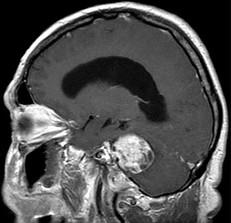

问题 听神经瘤(如图所示)的最常见症状为()

选项 A.头痛、呕吐 B.面部麻木,痛觉减退 C.眩晕,单侧耳鸣,耳聋 D.吞咽困难,进食呛咳 E.小脑运动共济失调

答案 C